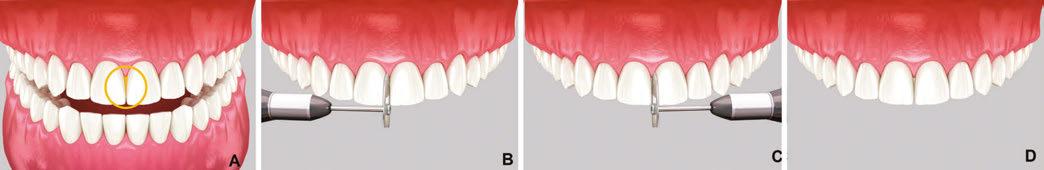

For cases where there is no overlapping of adjacent teeth, diamond-coated disks (Superflex, SS White, Lakewood, New Jersey) can be effectively used. These disks, available in single and double-sided options (Figure 5), are mounted on a slow-speed straight nose handpiece. To prevent accidental soft tissue injury, the use of a lip retractor is recommended. Due to the potential for soft tissue damage, the use of diamond-coated disks is primarily restricted to the anterior region (maxillary and mandibular).

When using a single-sided disk, the proximal surface of one tooth is modified first (Figure 6B), followed by the adjacent tooth after repositioning the handpiece 180 degrees (Figure 6C). For optimal results, the disk should be aligned parallel to the desired midline or vertical axis.

in coarse, medium, and fine grits (Figure 7), come in 4 mm and 2.5 mm widths to accommodate various clinical scenarios. The non-diamond coated center section of the strip allows for easy placement in tight contact areas.

To open a contact, the diamond abrasive surface of the strip is positioned at the tooth’s contact point. In posterior teeth, the strip is maintained parallel to the mesial or distal surface and gently pulled buccally and lingually to create a flat proximal surface. The strip is then reversed to modify the opposing proximal surface. To prevent food traps and facilitate subsequent orthodontic treatment, it is essential to avoid excessive reduction of the proximal contact area.

In the anterior region, where recontouring is aimed at correcting tooth width at the contact area, the strip is curved to follow the buccal-lingual curvature of the tooth (Figure 8B). The process is repeated on the adjacent tooth (Figure 8C).

When dealing with severe crowding, especially in the mandibular anterior, it is crucial to orient the strip to match the tooth’s proximal orientation being modified (Figure 9). This ensures a natural appearance following orthodontic treatment.

Figures 6A-6D